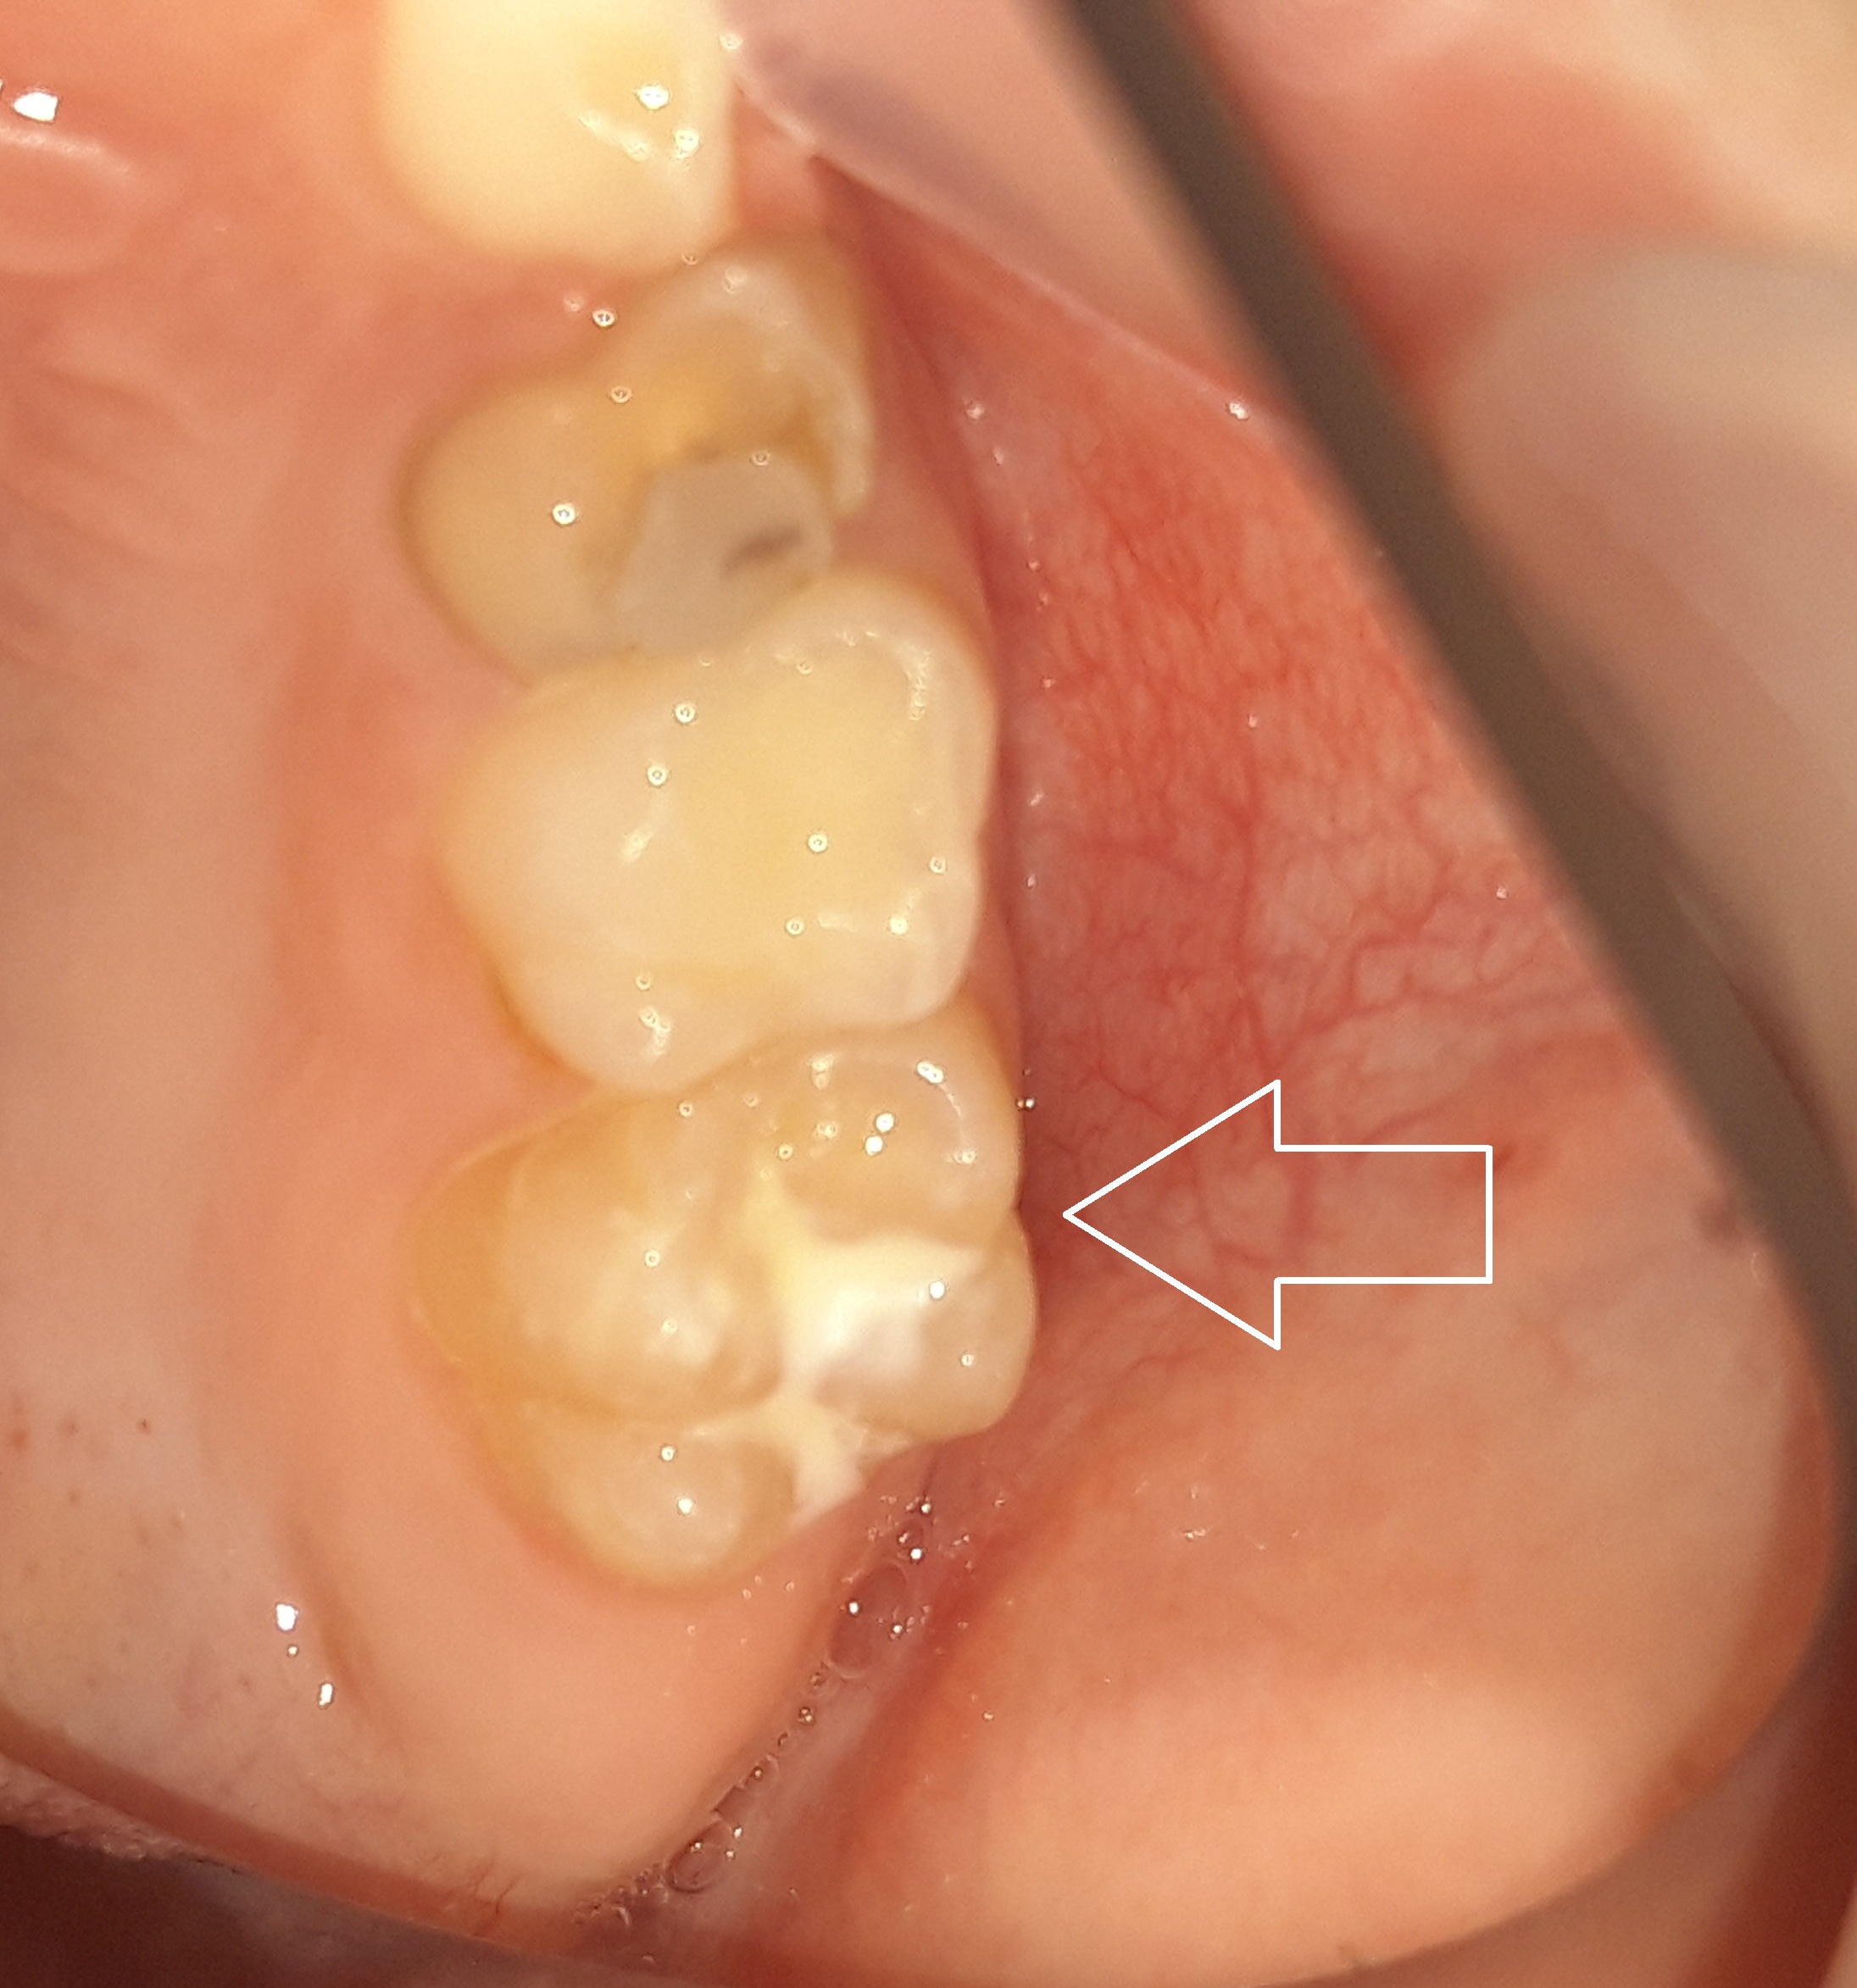

Περιστατικά – Sealant / προληπτική κάλυψη οπών και σχισμών

Στο συγκεκριμένο ασθενή πραγματοποιήθηκε ταυτόχρονα αφαίρεση της επιφανειακής αρχόμενης τερηδόνας και προληπτική κάλυψη οπών και σχισμών (sealant) στη μασητική επιφάνεια του άνω αριστερού πρώτου γομφίου.